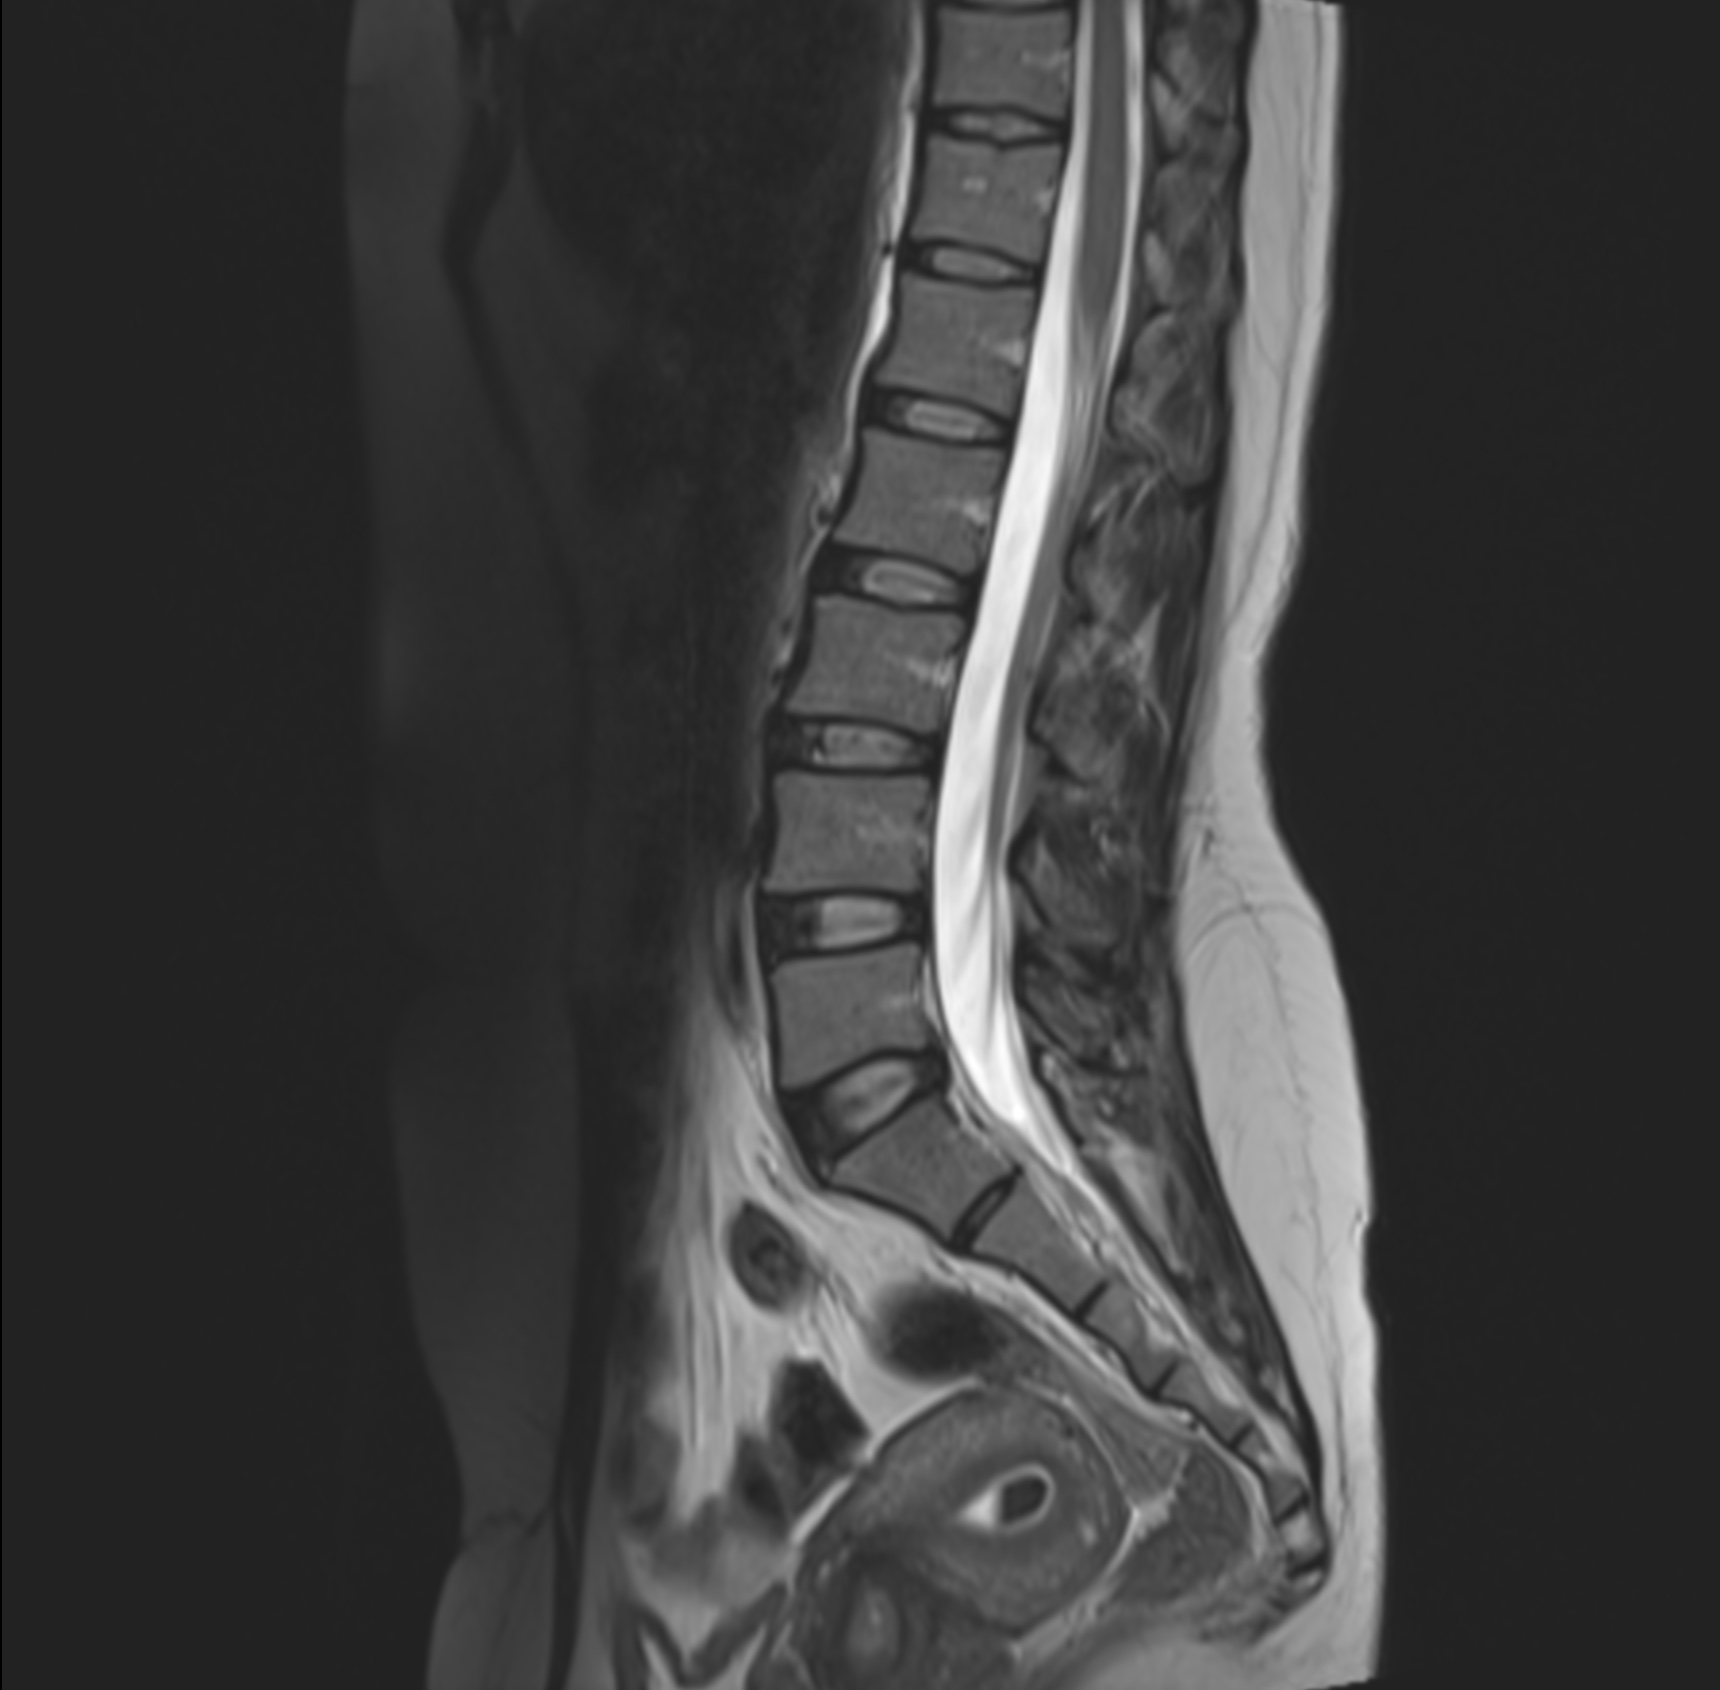

RM de columna lumbar

Nuestro examen de resonancia magnética en la zona lumbar detecta , vigila lesiones en huesos, ligamentos y sistema nervioso como la médula espinal. También diagnostica tumores, hemorragias, hinchazón, inflamaciones en las vértebras, etc.